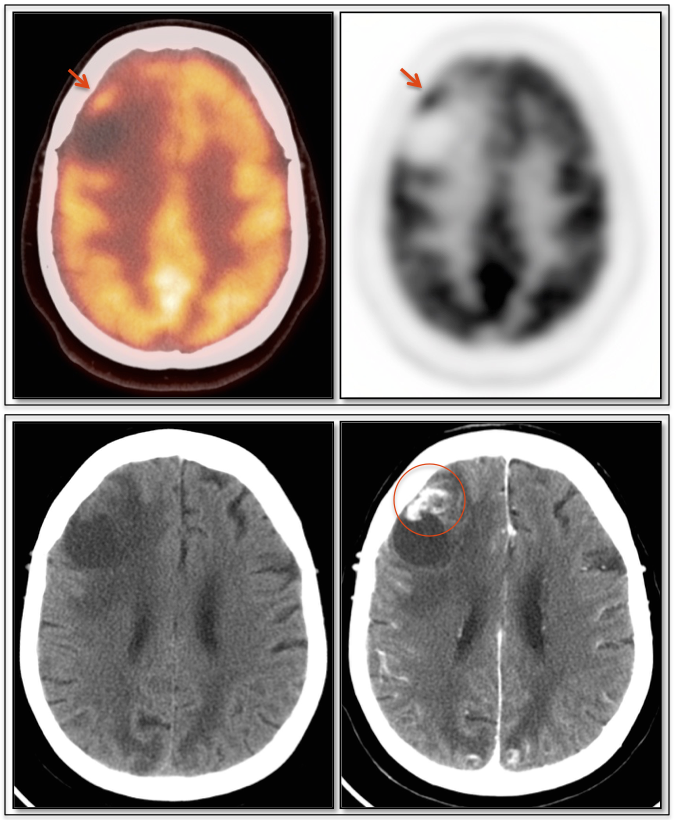

Brain Metastases:

- Far more common than primary lesions (> 10 times).

- If small and at grey-white junction, can be easily overlooked.

- Commonly from lung, breast, melanoma and GI primaries.